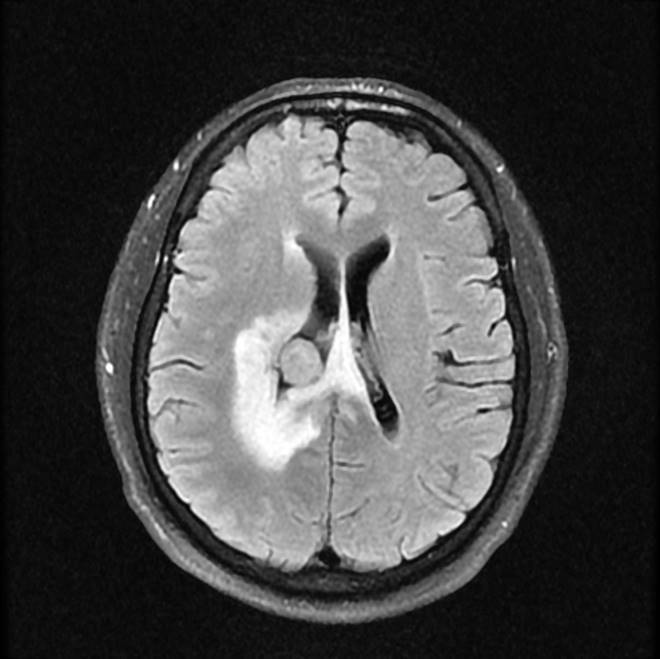

磁共振影像圖

圖3

MR診斷:右側(cè)側(cè)腦室三角區(qū)及側(cè)腦室旁占位,考慮惡性腫瘤可能,間變型腦膜瘤?轉(zhuǎn)移瘤?

CT是腦腫瘤的常用檢查方法,CT平掃及增強通過腫瘤的形態(tài)、密度及血供情況等對腦膜瘤的診斷和鑒別診斷有一定的價值。腦膜瘤為腦外腫瘤,但瘤周腦實質(zhì)水腫的出現(xiàn)率也較高,國外報道約60%。本例非典型腦膜瘤可見顯著的瘤周水腫。導致瘤周水腫的機制仍不明確,可能由多種因素參與、共同影響、相互制約所引起的一種血管源性水腫,腫瘤壓迫鄰近引流靜脈容易產(chǎn)生水腫,也有學者認為與腫瘤的血管內(nèi)皮生長因子、水通道蛋白-4高表達等因素有關。

MR鑒別診斷

常規(guī)MR檢查是診斷腦膜瘤的有效手段,可以明確腫瘤發(fā)生的部位、形態(tài)和數(shù)目等特征以及病變向鄰近腦實質(zhì)侵犯的程度和范圍,典型腦膜瘤呈等或(和)稍長T1、等或(和)稍長T2信號,??娠@示完整的包膜,增強掃描因腫瘤內(nèi)部新生血管通透性不同呈不同程度強化,由于腫瘤組織的強化程度與腫瘤的惡性程度不完全一致,導致MR常規(guī)檢查在腦膜瘤分級分型方面仍存在一定的困難。擴散加權成像( diffusion weighted imaging,DWI) 及表觀擴散系數(shù)( apparent diffusion coefficient,ADC) 被廣泛用于腦腫瘤的分級、分子分型和腫瘤侵襲性預測,并取得了良好的性能。目前,對于非典型腦膜瘤腦實質(zhì)侵犯的診斷的金標準依賴于組織病理學。